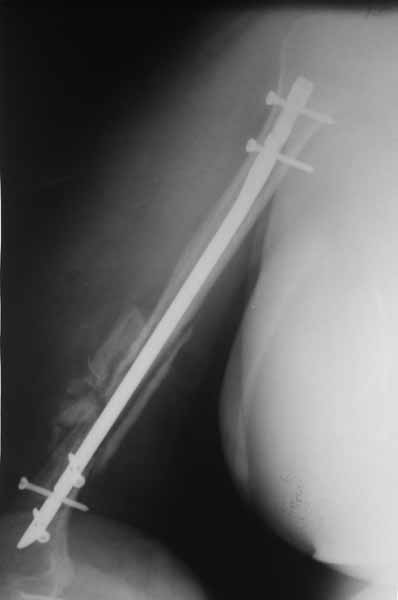

Доброго времени суток уважаемые коллеги.Представляю вашему вниманию пациентку 54 лет.Из анамнеза: травма в сентябре 2010 года в результате падения. В ЦРБ по м/ж выполнена открытая репозиция, синтез штифтом Кюнчера и проволочным серкляжами.

Спустя 6 месяцев после операции пациентка госпитализирована к нам в клинику. После выполнения контрольных рентгенограмм помимо атрофичного ложного сустава н\3 плечевой кости был диагностирован нижний вывих головки плечевой кости.

Первым этапом выполнено удаление металлоконструкции и БИОС плечевой кости с костной аутопластикой плечевой кости. Послеоперационный период без особенностей. Пациентка получила полный курс электромиостимуляции.